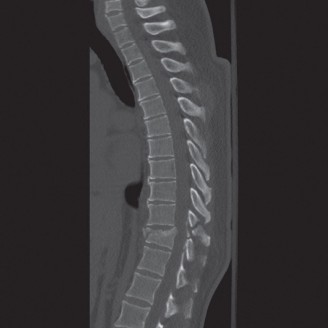

The correct answer is (A). As the case scenario strongly suggests an injury to the spine at the thoracolumbar junction, a CT scan of both the thoracic and lumbar regions is indicated. An MRI should not be the first imaging study obtained. Standing films should not be obtained in a trauma patient with a potentially unstable spine injury. A CT myelogram would only be obtained if an MRI was indicated but the patient had a contraindication to an MRI. Images of the above patient are shown inFigures 1–25 and 1–26. This injury is best characterized as which of the following? 1. Compression fracture

Figure 1–25

Figure 1–26

The correct answer is (B). The images demonstrate an L1 vertebral body fracture with a small degree of kyphosis. There is comminution of the vertebral body with a posterior vertebral body fragment that is slightly retropulsed into the spinal canal. This separate posterior vertebral body fragment (which is noncontiguous with the pedicles) is the hallmark of a burst fracture. Compression fractures do not have any posterior vertebral body involvement. A Chance fracture, also known as a seat belt fracture or flexion–distraction injury, will exhibit distraction of the posterior elements through bone, bone-ligament, or purely ligament structures, with an axis of rotation somewhere within the anterior vertebral body or anterior to the vertebral body. A fracture dislocation exhibits translational deformities between the injured levels. While there appears to be a translational deformity on the sagittal CT, the vertebral bodies of the uninjured levels above and below are actually well aligned.